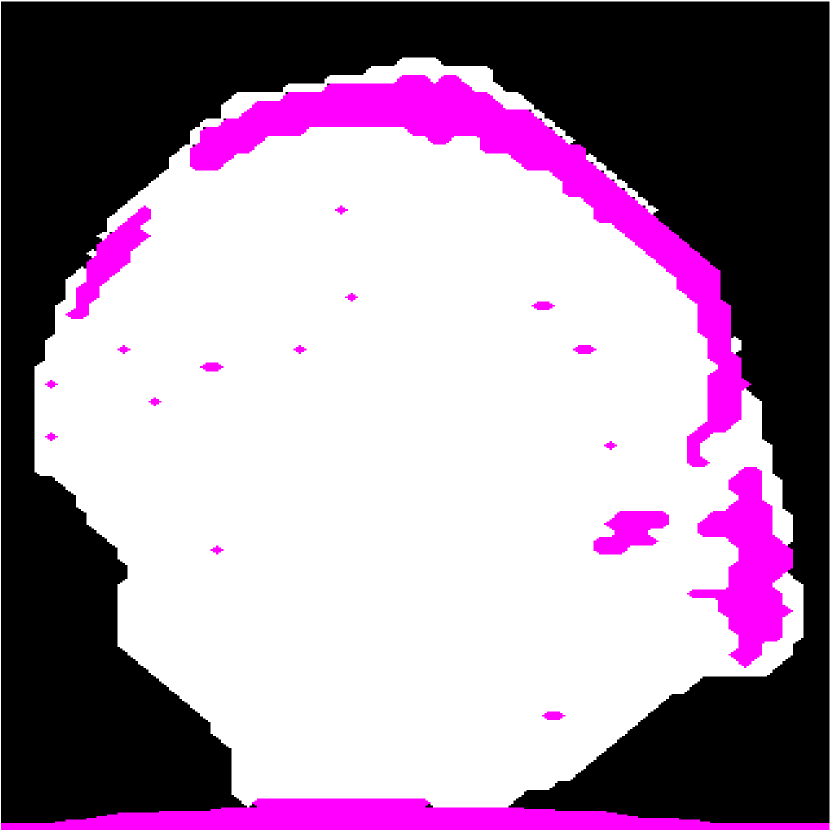

Figure 1(a) shows a representative HFU image of a human LN immersed in a phosphate-buffered saline (PBS) bath. Two different LN tissue types are visible: LNP (inside) and fat (surrounding). In order to perform QUS processing successfully, a 3D segmentation method is required to restrict QUS processing to LNP and to correct accurately for ultrasound attenuation [2]. Furthermore, accurate segmentation can provide detailed LNP shape information, which can be used to produce additional bio-markers of cancer.

Automatic LN segmentation in HFU images faces several challenges, such as speckle noise, low contrast between LNP and fat, implicit boundary and spatially varying intensity distributions caused by acoustic attenuation and focusing effects. Therefore, obtaining satisfactory results with intensity information alone is not possible. To illustrate this point, Figure 1(c) shows the result of a K-means analysis, which clusters voxels based on their intensities. Compared to manual segmentation result, some LNP voxels with high intensity are mislabeled as fat, and some LNP voxels with low intensity are mislabeled as PBS. Due to speckle noise and spatially varying intensity distributions in HFU images, other intensity-based segmentation methods such as region growing [7] would also yield unsatisfactory results.

Figure 1: (a) Target HFU image. (b) Manual-segmentation result by an expert. LNP is white and fat region is pink. The vertical axis is depth. (c) The segmentation result obtained by K-means.